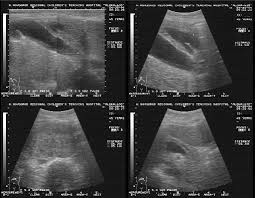

Симптомы и диагностика: Симптомы рака головки поджелудочной железы могут быть неясными и включать желтуху, потерю веса и боли в животе. Это приводит к тому, что заболевание часто выявляется на более поздних стадиях. Использование современных методов визуализации, таких как МРТ и КТ, а также биопсия, может помочь в более ранней диагностике.